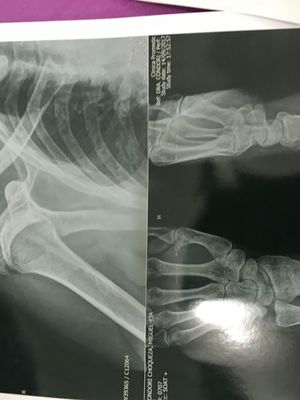

Fracture

Radiography